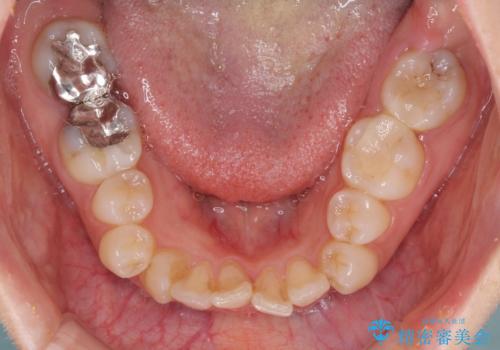

- 前歯の著しいデコボコを気にして来院された患者様です。

上顎の左右側切歯(前から2番目)が裏側に隠れいてる状態で、咬み合わせや清掃性に大きな問題が認められました。

左下に八重歯があったそうですが、当時は矯正治療を行うことを考えていなかったため、抜歯してしまったとのことでした。

叢生が著しいため、左下以外の第一小臼歯3本を抜去し、目立たないワイヤー装置にて矯正治療を行うこととしました。